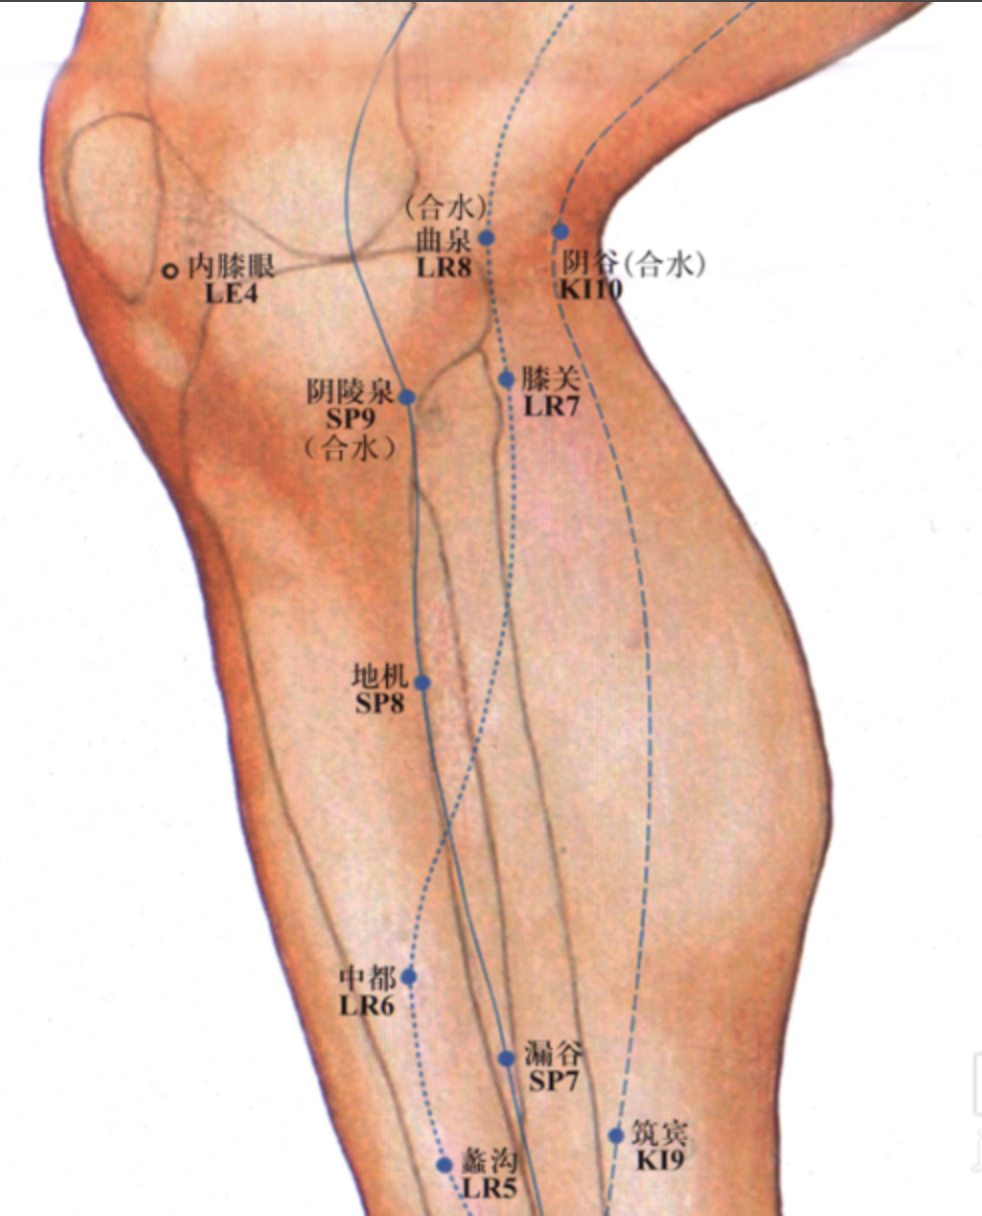

【(十二)足厥阴肝经(图10-30-1)】

1、时辰 丑时 1 ~ 3

2、歌诀 一十四穴足厥阴,大敦行间太冲侵,中封蠡沟中都近,膝关曲泉阴包临,五里阴廉急脉穴,章门常对期门深。

3、经脉循行 起于足大趾上毫毛部(大敦),经内踝前向上至内踝上 8 寸处交出于足太阴经之后,上行沿股内侧,进入阴毛中,绕阴器,上达小腹,夹胃旁,属肝络胆,过膈,分布于胁肋,沿喉咙后面,向上入鼻咽部,连接于“目系”(眼球联系于脑的部位),上出于前额,与督脉汇合于巅顶。

“目系”支脉:下行颊里、环绕唇内。

肝部支脉:从肝分出,过膈,向上流注于肺,与手太阴肺经相接。

4、主要病候 腰痛、胸满、呃逆、遗尿、小便不利、疝气、少腹肿等证。

5、主治概要 主治肝病、妇科、前阴病及经脉循行部位的其他病证。

曲泉

【定位】 在膝内侧,屈膝,当膝关节内侧端,股骨内侧髁的后缘,半腱肌、半膜肌止端的前缘凹陷处。

【主治】 月经不调,痛经,带下,阴挺,阴痒,产后腹痛,遗精,阳痿,疝气,小便不利,头痛,目眩,癫狂,膝髌肿痛,下肢痿痹。

【配伍】 配丘墟、阳陵泉治胆道疾患,配肝俞、肾俞、章门、商丘、太冲治肝炎,配复溜、肾俞、肝俞治肝肾阴虚之眩晕,翳障眼病,配支沟、阳陵泉治心腹疼痛、乳房胀痛、疝痛,配归来、三阴交治肝郁气滞之痛经、月经不调。

【刺灸法】 直刺 1 ~ 1.5 寸;可灸。

【附注】 肝经合穴。